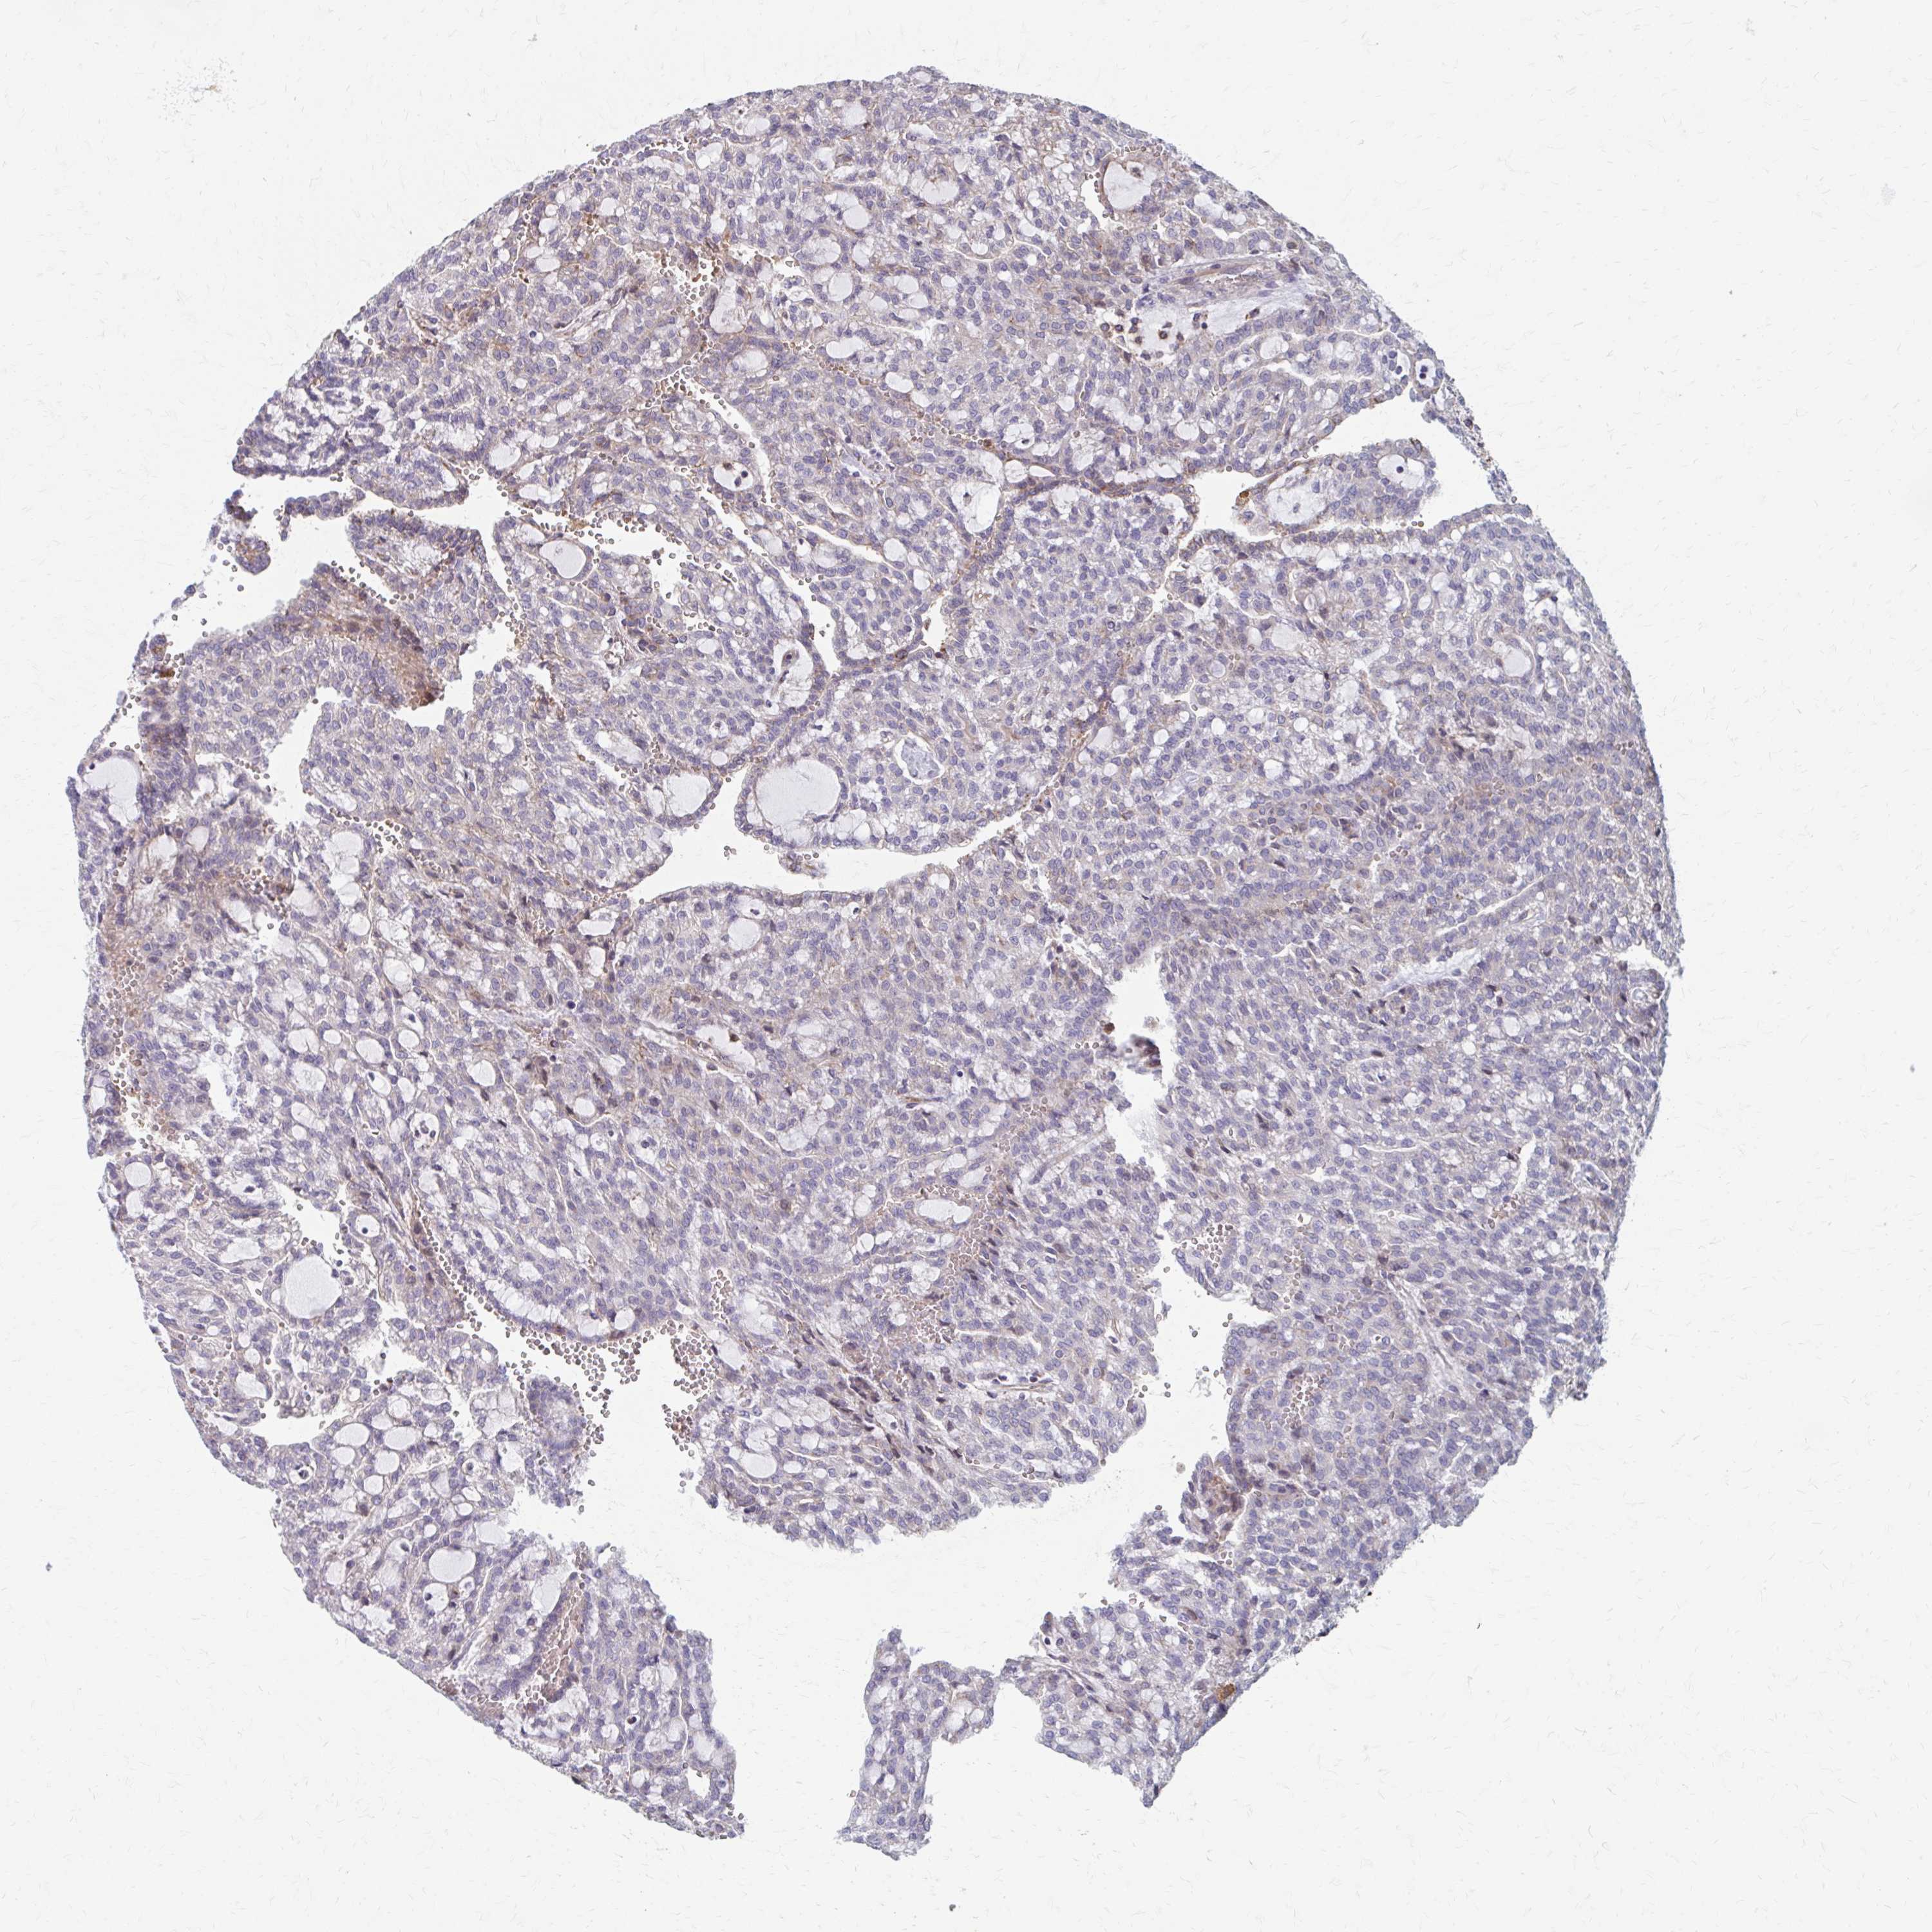

CANCER RENAL CANCER Show tissue menu

Renal cancer

Kidney chromophobe